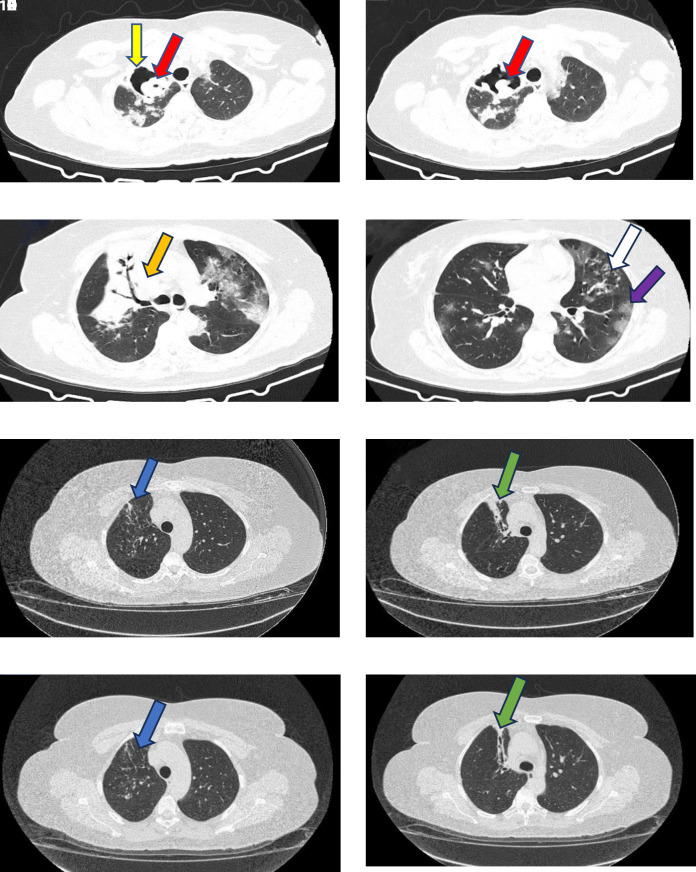

Case presentation: A 48-year-old female patient from the Central West of Brazil was admitted with a history of cough, yellow sputum, fever, and significant weight loss for two months. The respiratory symptoms worsened one week before admission. She tested positive for COVID-19 by RT-PCR. She had a history of hypertension and diabetes. Clinical examination revealed tachypnea, slurred speech, and hypoxia. She presented with hyperglycemia, obesity, hypertension, and an episode of hemoptysis. Chest CT revealed cavitation in the right upper lobe with a 45 mm aspergilloma, multifocal morning opacities, and nodular opacities. Laboratory tests confirmed the PTB with positive sputum for acid-fast bacilli and positive culture for Mycobacterium tuberculosis. The sputum culture also showed Aspergillus spp. She received early treatment for bacterial pneumonia with ceftriaxone, dexamethasone, enoxaparin, an anti-TB regimen, and itraconazole. There was a progressive clinical improvement and the patient was discharged after 15 days. She completed six months of anti-TB therapy and 13 months of itraconazole treatment for CPA, with complete resolution of the cavitation and aspergilloma.

Discussion and conclusion: This case study presents a unique case of CPA that manifested as simple aspergilloma and was diagnosed concurrently with the initial episode of PTB in a COVID-19 patient with obesity, hypertension, and diabetes. Remarkably, the fungal ball and cavitation regressed spontaneously. The favorable clinical and radiological results highlight the importance of comprehensive treatment approaches for concurrent respiratory infections and emphasize the need to investigate CPA and PTB during COVID-19 hospitalization.